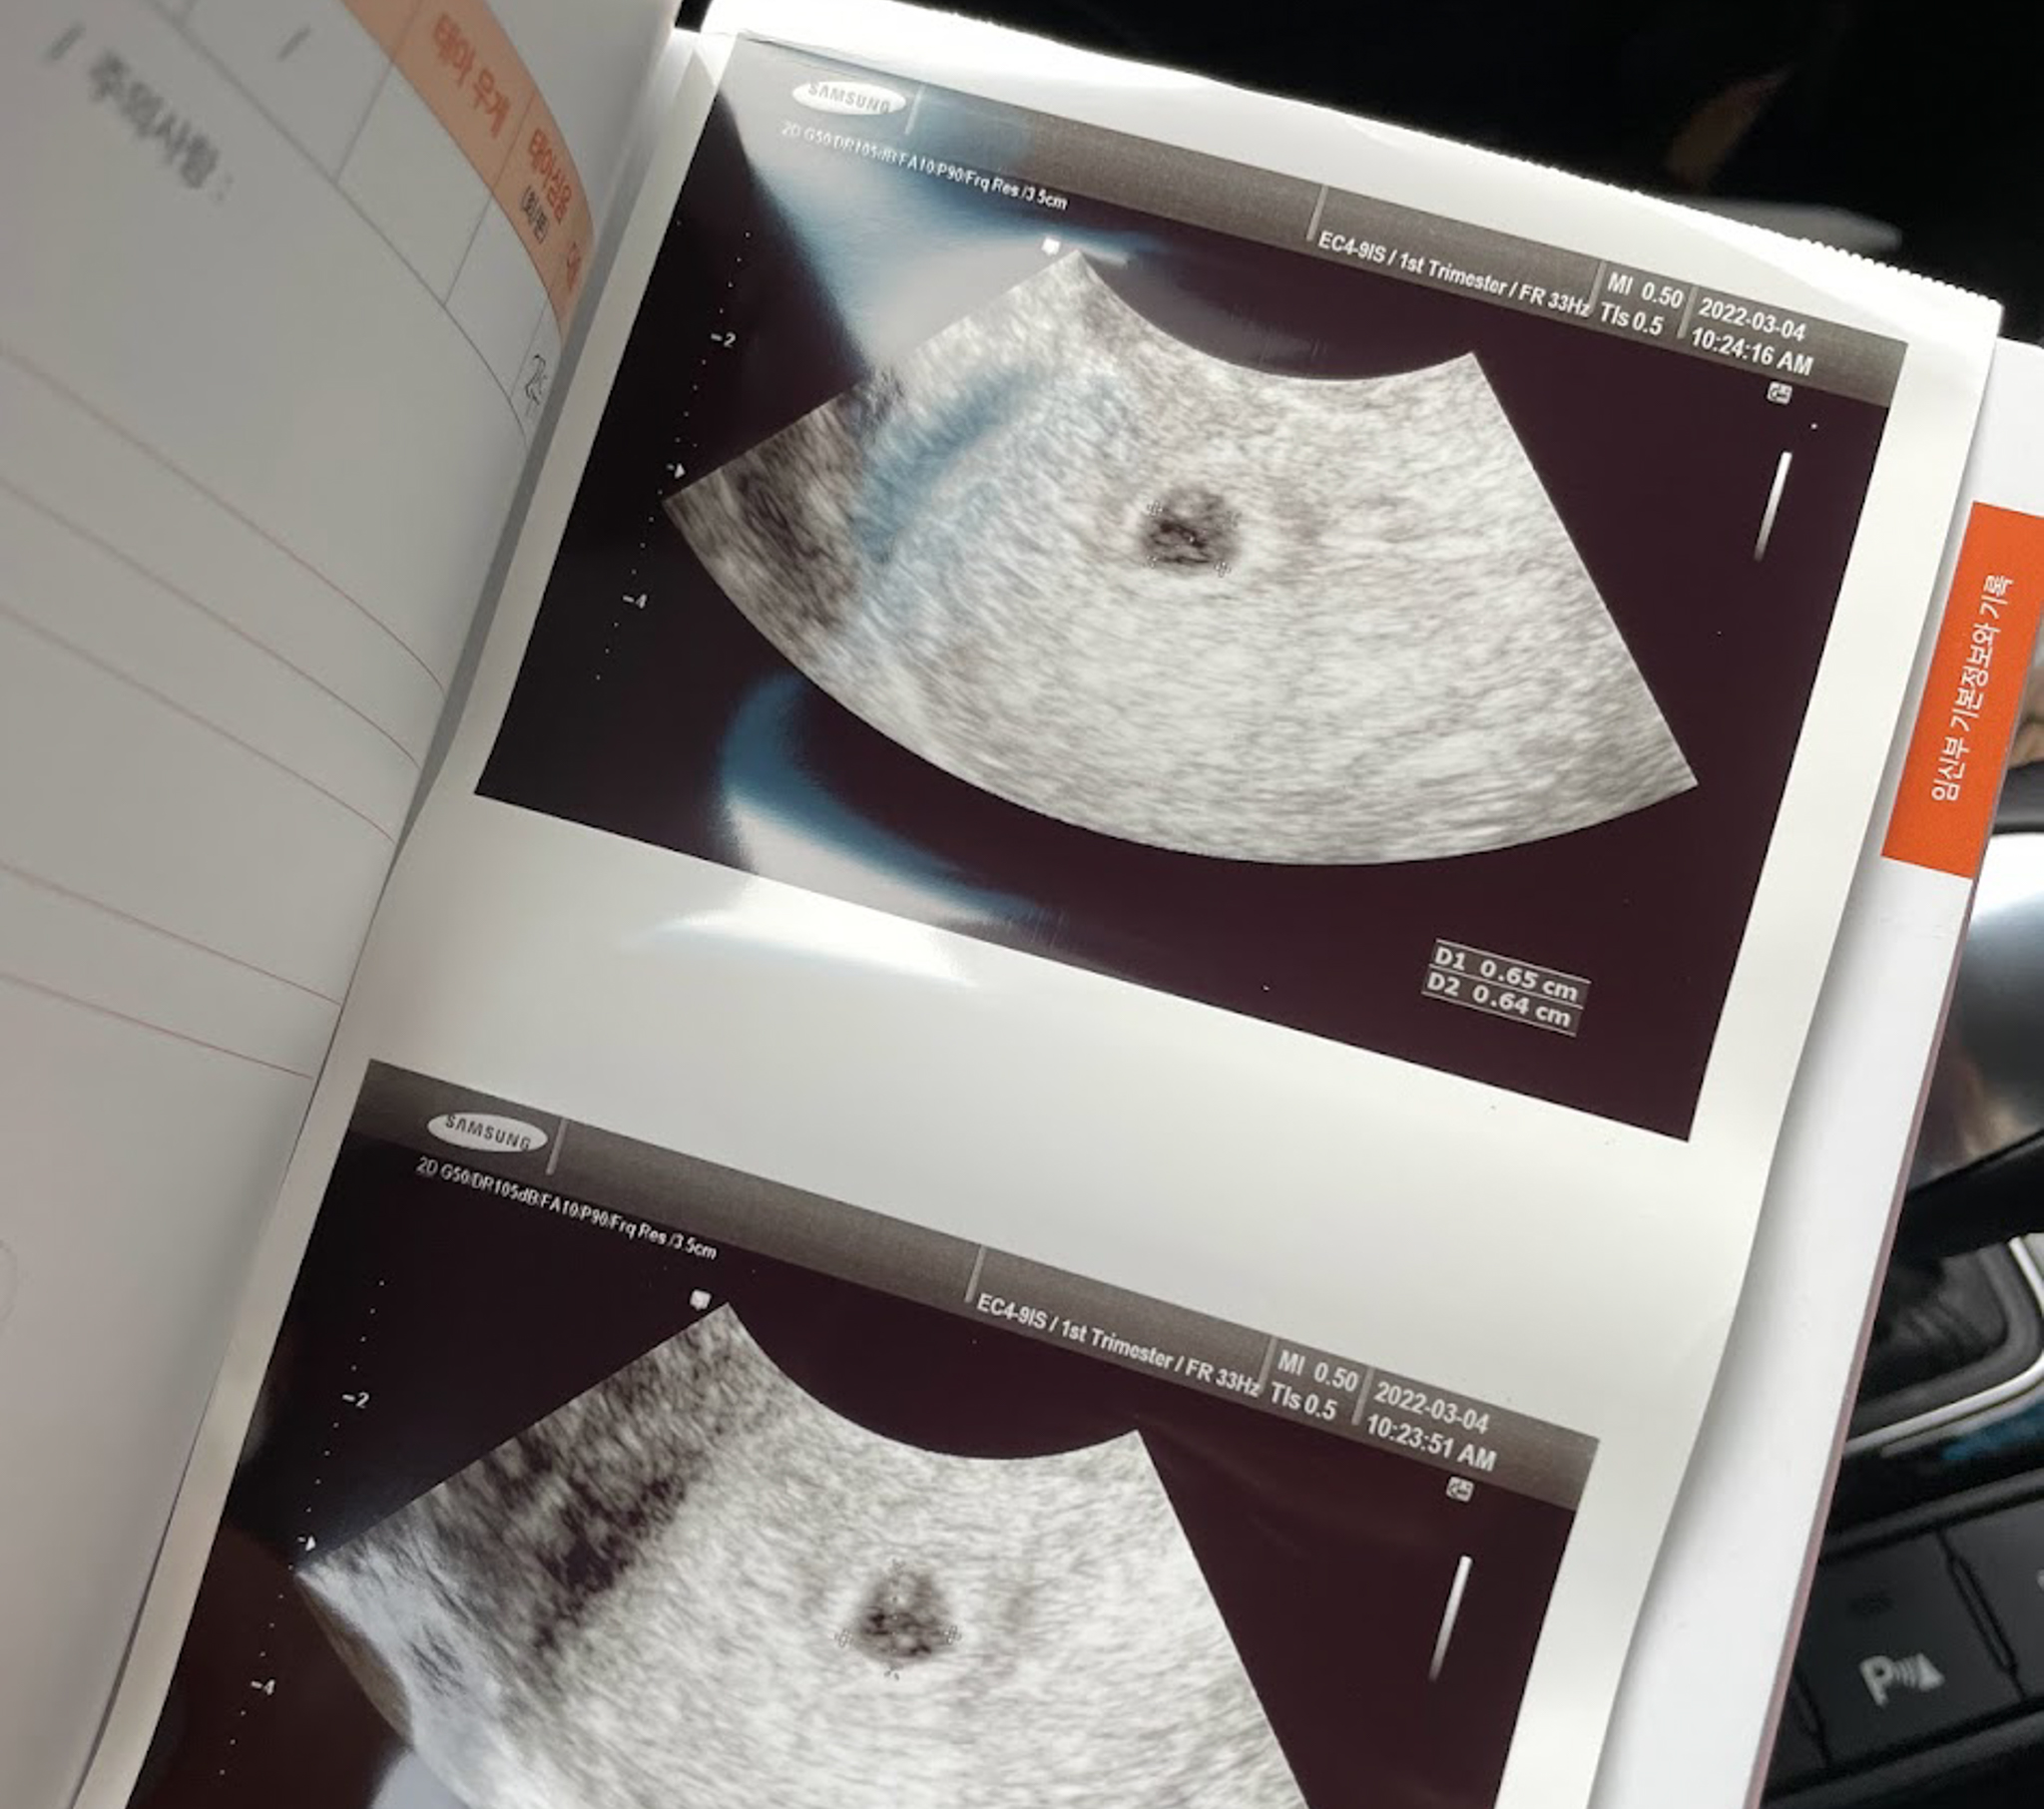

03. 04

지환이 때 다니던 병원은 이제 분만을 안한다해서

새로운 병원으로.

아기집이 확인되서 임신확인서도 받아왔다.

조리원 상담도 받고,

집에와서 바우처도 신청했다.

아직도 얼떨떨...